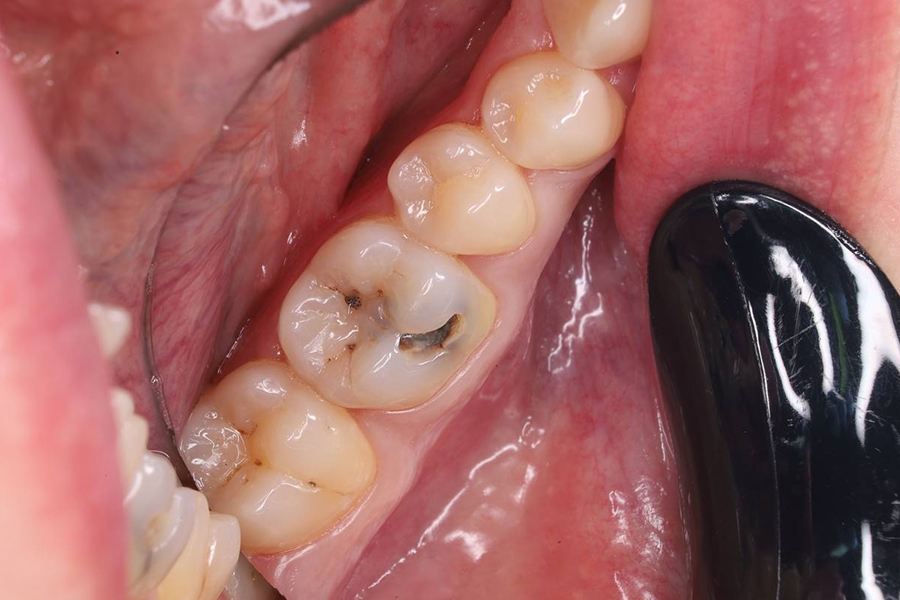

ЖалобыИзменение цвета зуба, наличие полости в зубе, а так же на кратковременную боль на холодное

Лечение кариеса с дальнейшим восстановлением коронки зуба с помощью светоотверждаемой пломбы :

1. Под местной анестезией после качественной изоляции было проведено вычищение патологической ткани с дальнейшей постановкой анатомической светоотверждаемой пломбы

• Вычищение патологической ткани